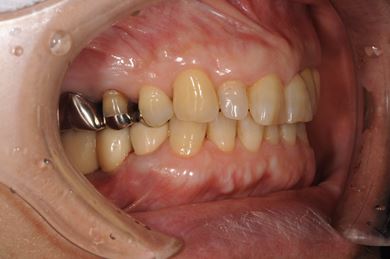

インプラントの症例写真 IMPLANT

骨再生スピードインプラント治療+セラミック治療

| 性別/年齢 | 女性 / 58歳 | ||||||||||||||||||||||||||||||||

| 主訴 | 左上前歯となりがゆらついている。他院でインプラントが必要と言われ、相談に来ました。 | ||||||||||||||||||||||||||||||||

| 治療方針 | 骨再生法によりインプラント治療を可能にする。抜歯と同時にインプラント埋入を行い、治療期間を短縮する。 | ||||||||||||||||||||||||||||||||

| 治療内容 | インプラント3本(抜歯即日スピードインプラント、GBR)、メタルボンドセラミッククラウン1本、ハイブリッドセラミッククラウン4本(ハイブリッドセラミック用土台1本) | ||||||||||||||||||||||||||||||||

| 総治療費 | 1,655,326円 | ||||||||||||||||||||||||||||||||

| 治療期間 | 1年3ヶ月 |